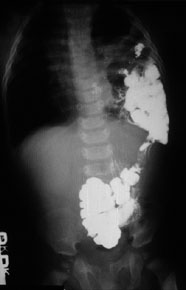

X-ray of patient with left-congenital diaphragmatic hernia (CDH), after barium meal.